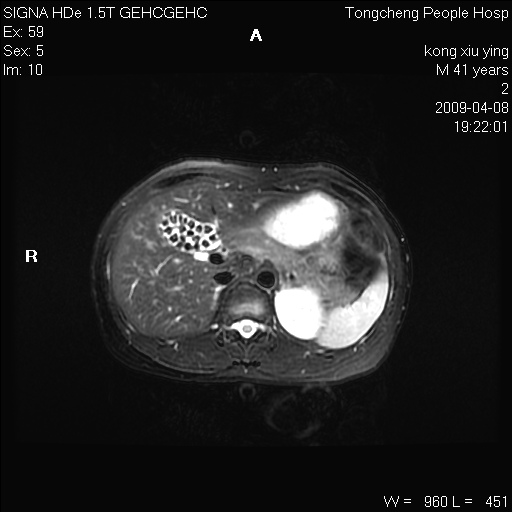

标题: CL1008:【经典】胆囊石榴籽样结石。

女,41岁。健康体检——彩超提示:胆囊显示不清。平素健康,无不适感。

腹部mr扫描及mrcp,图像如下: